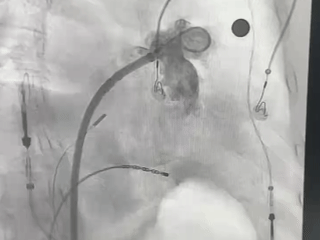

MemoLefort封堵器展开后DSA下充分评估

肝位即刻造影,位置合适,上下缘无造影剂漏

牵拉试验,牵拉后有明显回弹,位置无移动

展开后DSA下造影,观察封堵左心耳开口无残余分流,且封堵器放置位置理想,充盈整个心耳开口处。肝位牵拉有回弹,无任何相关位移。

压缩比测量

压缩比17.3%,在10%-30%之间,符合推荐压缩比

MemoLefort封堵器术中释放后造影评估

封堵器完全释放

肝位造影确认,封堵器位置合适,无残余漏

Lefort封堵器释放

Lefort封堵器评估符合PASS原则,释放封堵器,封堵器位置稳定且未见残余漏,封堵完美。